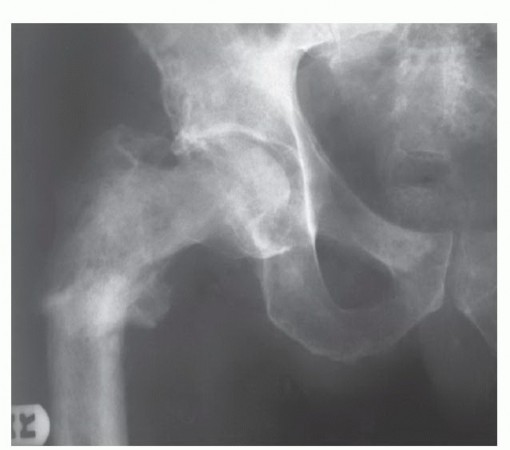

Epidemiologically, the femur is the most frequent site for both primary malignant bone tumors and skeletal metastases. Osteosarcoma and Ewing sarcoma exhibit a distinct predilection for the femoral metadiaphysis in the pediatric and adolescent populations, while chondrosarcoma frequently targets the proximal femur in adults. Furthermore, the proximal femur is the most common long bone affected by metastatic dissemination from breast, prostate, lung, renal, and thyroid carcinomas. The pathophysiology of these lesions dictates our surgical approach. Primary sarcomas expand radially, compressing surrounding normal tissue to form a reactive pseudocapsule, which must be resected en bloc with a continuous cuff of normal tissue to achieve negative oncologic margins (R0 resection). Conversely, metastatic lesions often present with catastrophic structural failure—the pathologic fracture—which contaminates the local tissue compartments with tumor cells, necessitating wider resections and more complex reconstructions.

Patient selection is the absolute foundation of successful megaprosthetic reconstruction. The indications for proximal and total femur replacement have expanded significantly over the past two decades, driven by advancements in implant survivorship and soft-tissue management. The classic indication remains the presence of a primary malignant bone sarcoma (osteosarcoma, chondrosarcoma, Ewing sarcoma) exhibiting extensive diaphyseal involvement that precludes the retention of a biomechanically viable segment of host bone. Furthermore, massive metastatic lesions—particularly those from renal cell or thyroid carcinoma, which are highly destructive and hypervascular—that present with impending or actual pathologic fractures are prime indications. In these metastatic scenarios, standard intramedullary nailing or plate osteosynthesis is doomed to fail due to the lack of structural bone stock and the inability of irradiated bone to heal; endoprosthetic replacement offers immediate structural stability and pain relief.